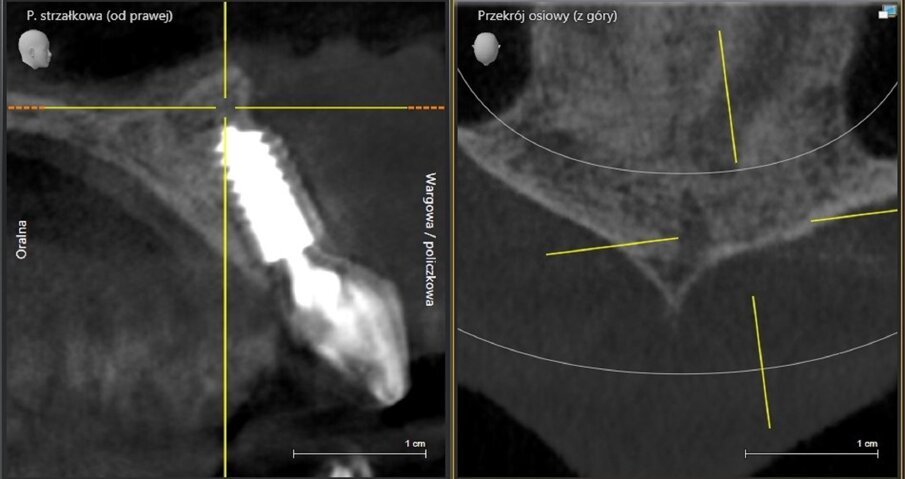

The implant apicectomy in Case 3 shows that one year after the immediate implantation with immediate loading there was inflammation around the implant apex. The rest was properly integrated (Figs. 13–20).

Fig. 14: Bone defect of 9.27mm in diameter.

Fig. 18: CBCT scan on the day of surgery. No bone augmentation.

Fig. 19: CBCT scan 1.5 years post-op. Visible bone regeneration.